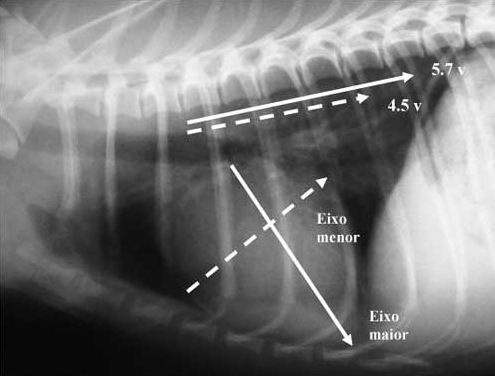

如上图,VHS=5.7v+4.5v=10.2v